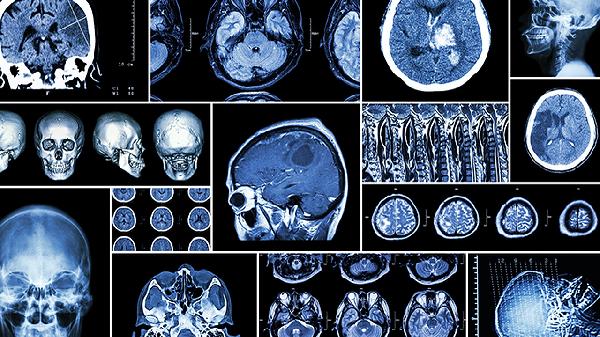

脑血栓患者除规范用药外,需保持低盐低脂饮食,每日钠盐不超过5克,增加蔬菜水果摄入。每周进行3-5次有氧运动如快走或游泳,每次30分钟。定期监测血压血糖,戒烟限酒,保证充足睡眠。若出现言语不清、肢体无力加重等表现,应立即就医复查头颅CT或MRI。